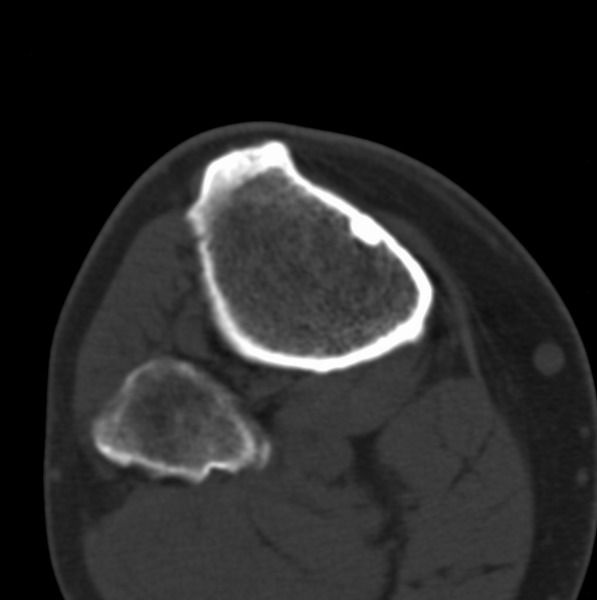

右侧膝关节疼痛一月

男、48

股骨下段、胫骨上段。

1、股骨干骺端病变考虑干骺端纤维性皮质缺损愈后(非骨化性纤维瘤)改变,胫骨近端内生骨瘤(或干骺端纤维性皮质缺损愈后改变);

2、骨关节炎,骨质增生,股骨外侧髁退变性囊肿(关节面软骨下囊肿);

3、髌骨前缘裂纹骨折?